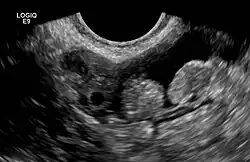

2 normal appendices epiploicae neben einem Eierstock im Ultraschall

Appendices epiploicae (Singular Appendix epiploica, von lateinisch appendix ‚Anhang‘ und griechisch ἐπίπλοον epiploonNetz‘) sind 1–4 cm lange, frei endende Fortsätze entlang der Taenia libera und Taenia omentalis des Colons (Colon ascendens, transversum, descendens, sigmoideum). Es handelt sich um von Serosa überzogene Fettgewebsauflagerungen. Sie halten die Kapillarität des Bauchhöhlenspalts während der Bewegung der Ausbuchtungen der Dickdarmwand (Haustren) aufrecht.[1]